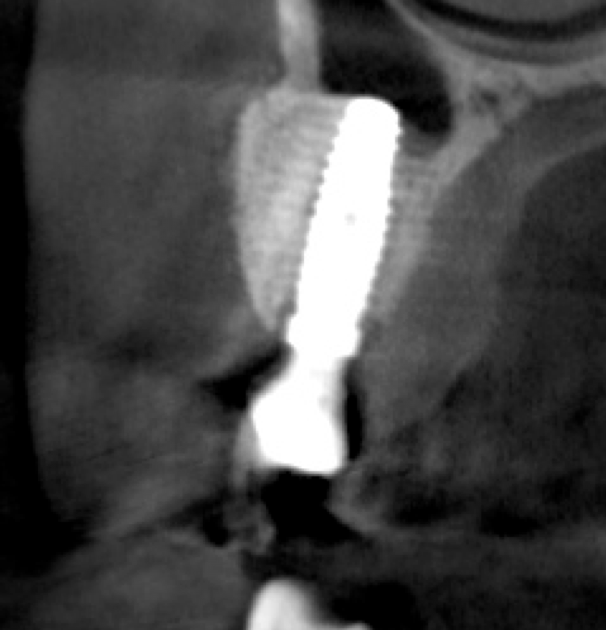

Tomographic images revealed a large tridimensional defect, with vertical and horizontal loss of bone extending to the apical third of teeth Nos. 6 and 8. Additionally, a buccal bone dehiscence was evident on tooth No. 5, and thin labial plates secondary to the orthodontic movement were present in several areas (Figure 3 and Figure 4).

Fig 3. Tomographic images revealed a tridimensional defect extending to the apical third of teeth Nos. 6 and 8, a buccal bone dehiscence on tooth No. 5, and associated thin labial plates.

Figure 3

Fig 10. Tomographic images of teeth Nos. 6 (Fig 10), 7 (Fig 11), and 8 (Fig 12) clearly showed vertical gains in alveolar height, including in the edentulous area corresponding to tooth No. 7. The apex of tooth No. 8 was located within the soft tissue because it was force-erupted beyond its socket.

Figure 10